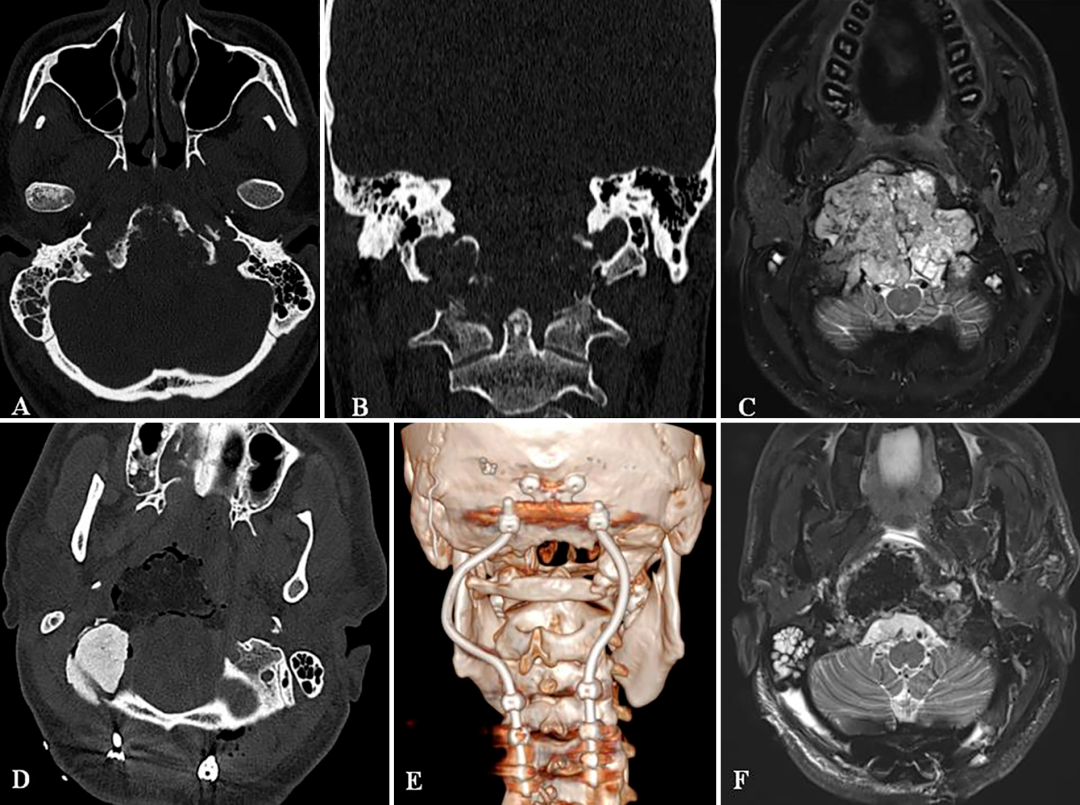

患者有慢性颈部疼痛病史1年,外院初次手术后5年复发,肿瘤尺寸51.3×74.3×25.9毫米,引起C2椎体病理性骨折及脊髓压迫。

治疗策略:采用神经内镜和显微镜双镜联合,使用前-远外侧入路一次全切肿瘤。

结果:术后MRI显示肿瘤完全切除,患者接受枕颈固定后无并发症,术后9个月无复发,神经功能正常,恢复日常活动。